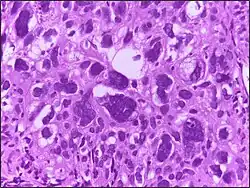

![]() | Malignant melanoma | Malignant spindle cell neoplasm, showing numerous mitotic figures, including atypical tripolar mitotic figure, in the centre. | Category: Histopathology of melanoma | Malignant melanoma |